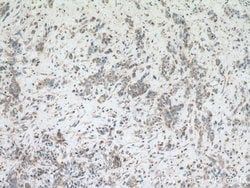

| Western Blot, Immunohistochemistry (Paraffin) | |